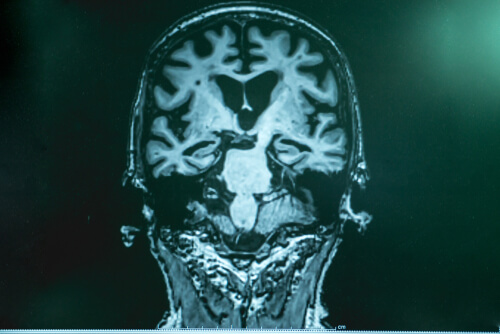

Dr. Lopera explains that, with Alzheimer’s disease, there’s a kind of accumulation of “garbage” in the brain. It’s made up of a protein called amyloid. Fragments of it stick together and form a kind of “glue” that sticks to the neurons and causes a number of malfunctions in the brain. The other part of the “garbage” is tau, which wraps around the neuron, “locks” it up, and kills it. Tau is more harmful.

After careful studies in Boston, experts found that the patient’s brain was filled with amyloid, even more than in other cases. However, she had very little tau. The research allowed them to verify that, in this particular patient, another mutation inhibited the production of tau and this was what delayed the progression of the disease.